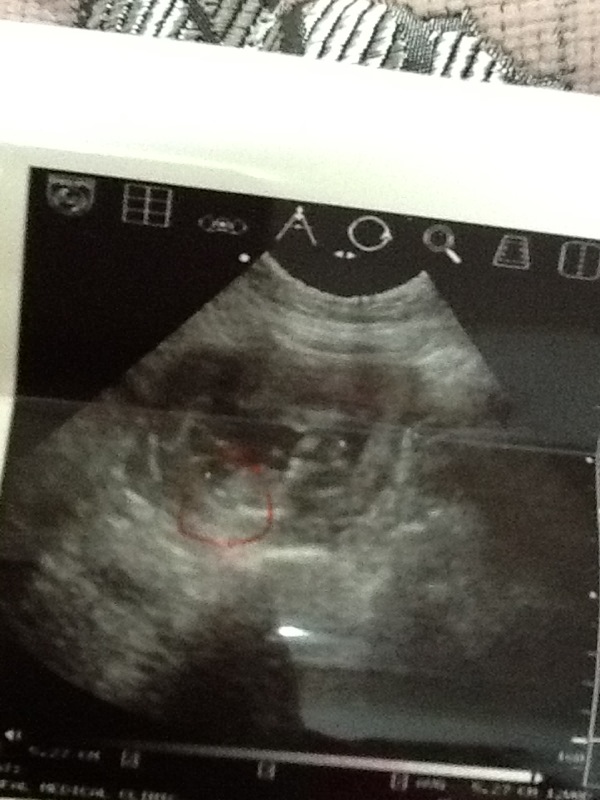

سديراويه إيه سويت ماكان واضح بنت او ولد بس الناب نازل تحت موازي للعمود الفقري الولد يكون فوق

بنزل الصور مره ثانيه تقولون وش لو تقول وحده مؤ واضح لا فجر فيها :mad:

وحدثت دائره باللون الأحمر ع الناب

جنيني توقف نبضه من اسبوعين وقرروا علي عملية تنظيف والحمد لله على قضاءه